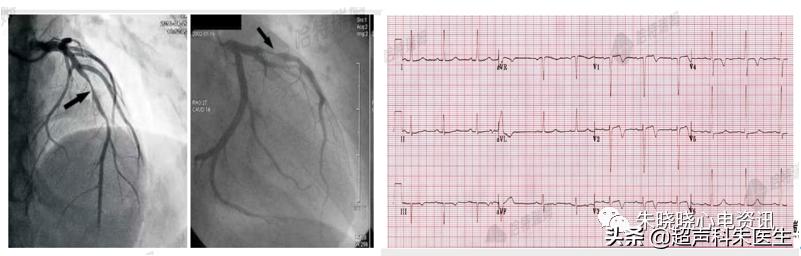

病例5:心尖部室壁瘤

图22:心尖部室壁瘤T波向量示意图

如图23所示,急性下侧壁心梗患者,2个月后复查心电图示下侧壁导联Q波形成,下壁导联和V3~V6导联中ST段抬高伴T波倒置,心脏彩超提示室壁瘤形成。

图23:室壁瘤与T波倒置

心尖部室壁瘤通常为急性心梗后室壁反复反向牵张,引起持续性ST段抬高与左室心肌反常运动。最常见的心电图表现为:ST段抬高,全导联或对应梗死部位的导联T波倒置;